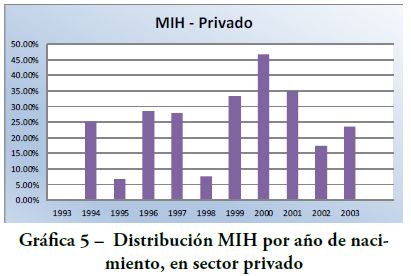

Los resultados intragrupo se representan en las Gráficas 1-6.

Distribución MIH según año de nacimiento

-Grupo 1 Sector Privado (Gráfica 5):

valor más alto de MIH en los nacidos en el año 2000 (7 niños); valor más bajo en los nacidos en 1993 (0 niño).

Teniendo en cuenta los resultados reportados con grupos de diferentes edades y coincidiendo con las recomendaciones de Jälevik(6) en 2010 sobre especificar la prevalencia en cada grupo de edad separadamente, en este trabajo el análisis de las muestras se realizó desglosado por año de nacimiento. Los resultados revelaron en ambos ámbitos de atención odontológica la prevalencia más alta en los niños nacidos en los años 2000 y 2001. Es probable que niños de mayor edad con MIH se excluyeran de la muestra por haber perdido molares o ser portadores de coronas, como consecuencia de esta patología(18).